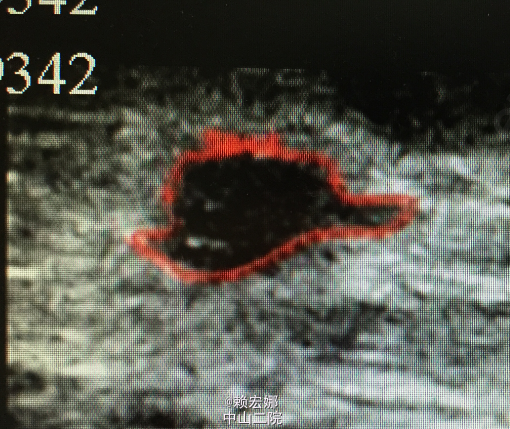

患者,女,31岁,发现左侧腋窝肿物1月

左侧腋窝可触及淋巴结肿大,大小约3cm,伴轻微疼痛感,双乳未触及明显肿物,无明显胸闷、乏力,无全身骨关节疼痛。外院B超:左侧乳腺实质性结节(增生结节可能,建议定期复查),左侧腋下低回声结节(考虑肿大淋巴结可能),建议进一步检查。我院B超:左乳实性低回声团,高度怀疑恶性病变(BI-RADS IVc类),建议住院手术。

患者术前检查未见明显禁忌症,局麻下行左乳肿物穿刺活检术,术后病理:(左腋下肿物)乳腺浸润性导管癌,II级,免疫组化:HER2(1+) ER (中至强+,80%)PR (-)Ki67(+,30%) P63(-) Calponin(-) E-cad (+)P53(+,10%)。患者乳腺癌诊断明确,遂在全麻下行左侧乳腺癌改良根治术,术后病理::1(左侧)乳腺浸润性导管癌,II级;2、乳头、四侧切缘和基底切缘未见癌浸润;3、(腋窝)淋巴结见癌转移(4/10),前哨淋巴结未见癌转移(0/2)。患者术后恢复良好,且未见明显化疗禁忌症,予以“表柔比星+紫杉醇脂质体”,化疗期间患者诉稍感恶习,无呕吐、乏力不适。